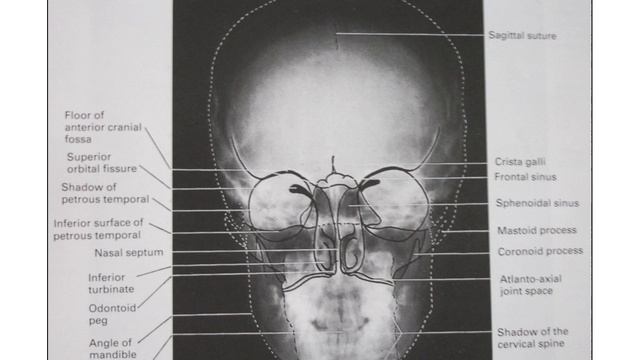

Extraoral Radiography & Indication | Oral Medicine and Radiology | BDS | 00841 | PPT Only смотреть онлайн

03:14

Extraoral Radiography & Indication | Oral Medicine and Radiology | BDS | 00841 | PPT Only